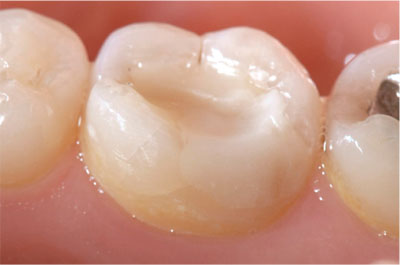

As a consequence of increased dental awareness in society, coupled with improvements in dietary and oral hygiene practices, many more patients, particularly younger patients, are now presenting with fewer and smaller lesions of caries than in the past (Figs 1-1 and 1-2). Such patients expect minimally interventive procedures, preferably using techniques that are described as “aesthetic” or “tooth coloured” (Fig 1-3). This, in association with commercial developments in composite resin materials and associated bonding technologies and lingering concerns over the safety of dental amalgam, has driven an increase in the placement of posterior composite restorations in general dental practice. For example, a survey of United Kingdom general dental practitioners in 2001 revealed, far from limiting the placement of composite to small cavities in premolar teeth, that almost one-half of general dental practitioners placed composite resin restorations in load-bearing cavities in molar teeth (Figs 1-4 to 1-6).

Fig 1-4 A posterior composite restoration that has been in clinical service for over eight years.